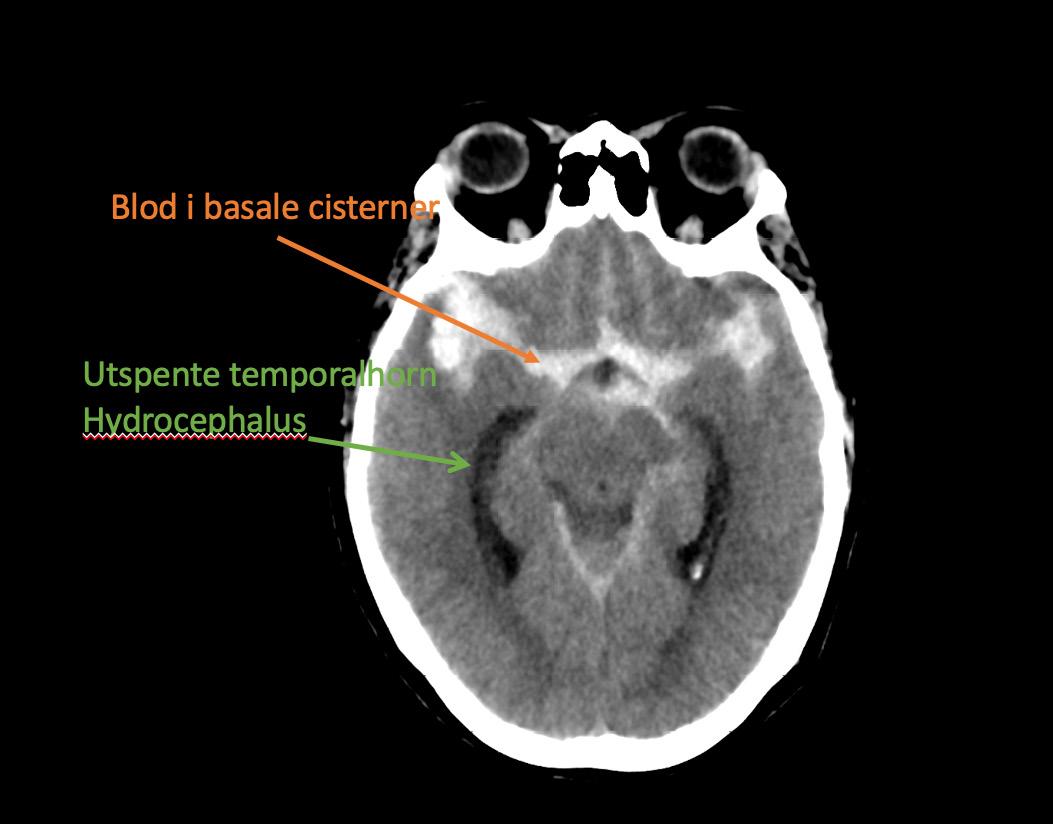

Bilde 1: Hyperdensiteter (blod) i basale cisterner og utspente temporalhorn er kjennetegn ved CT-scanning av en SAH med hydrocefalus.

CT caput er den raskest tilgjengelige og beste initiale diagnostiske test ved spørsmål om aSAH. Sensitiviteten til CT forblir svært høy for å avdekke blod i subaraknoidalrommet de første 3 døgn etter iktus (11) (Bilde 1).